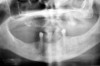

Figure 4  Radiograph of oral bisphosphonate user.

Figure 4

Under the sextant approach, one quadrant is treated and the patient is left to heal for 2 months before proceeding to any additional quadrants. While the patient heals, a 10-day course of antibiotics and 2 months of twice-daily chlorhexidine rinsing may be prescribed. Figure 4 shows a patient who was taking oral bisphosphonates for 3 years and was treated with the sextant approach. As seen in the radiograph, the patient has one molar in the lower right quadrant. This tooth was extracted and the patient was given 2 months to heal (Figure 5 and Figure 6). The patient was placed on antibiotics and chlorhexidine rinse. After 2 months, no signs of BRONJ were observed, and the anterior teeth were scheduled for extraction. They were extracted as atraumatically as possible, and the site was sutured (Figure 7 and Figure 8). The patient then was given another 2 months to heal, following the previous protocol. After 2 months of healing, no BRONJ was observed (Figure 9). The patient was able to move forward with the prosthesis.